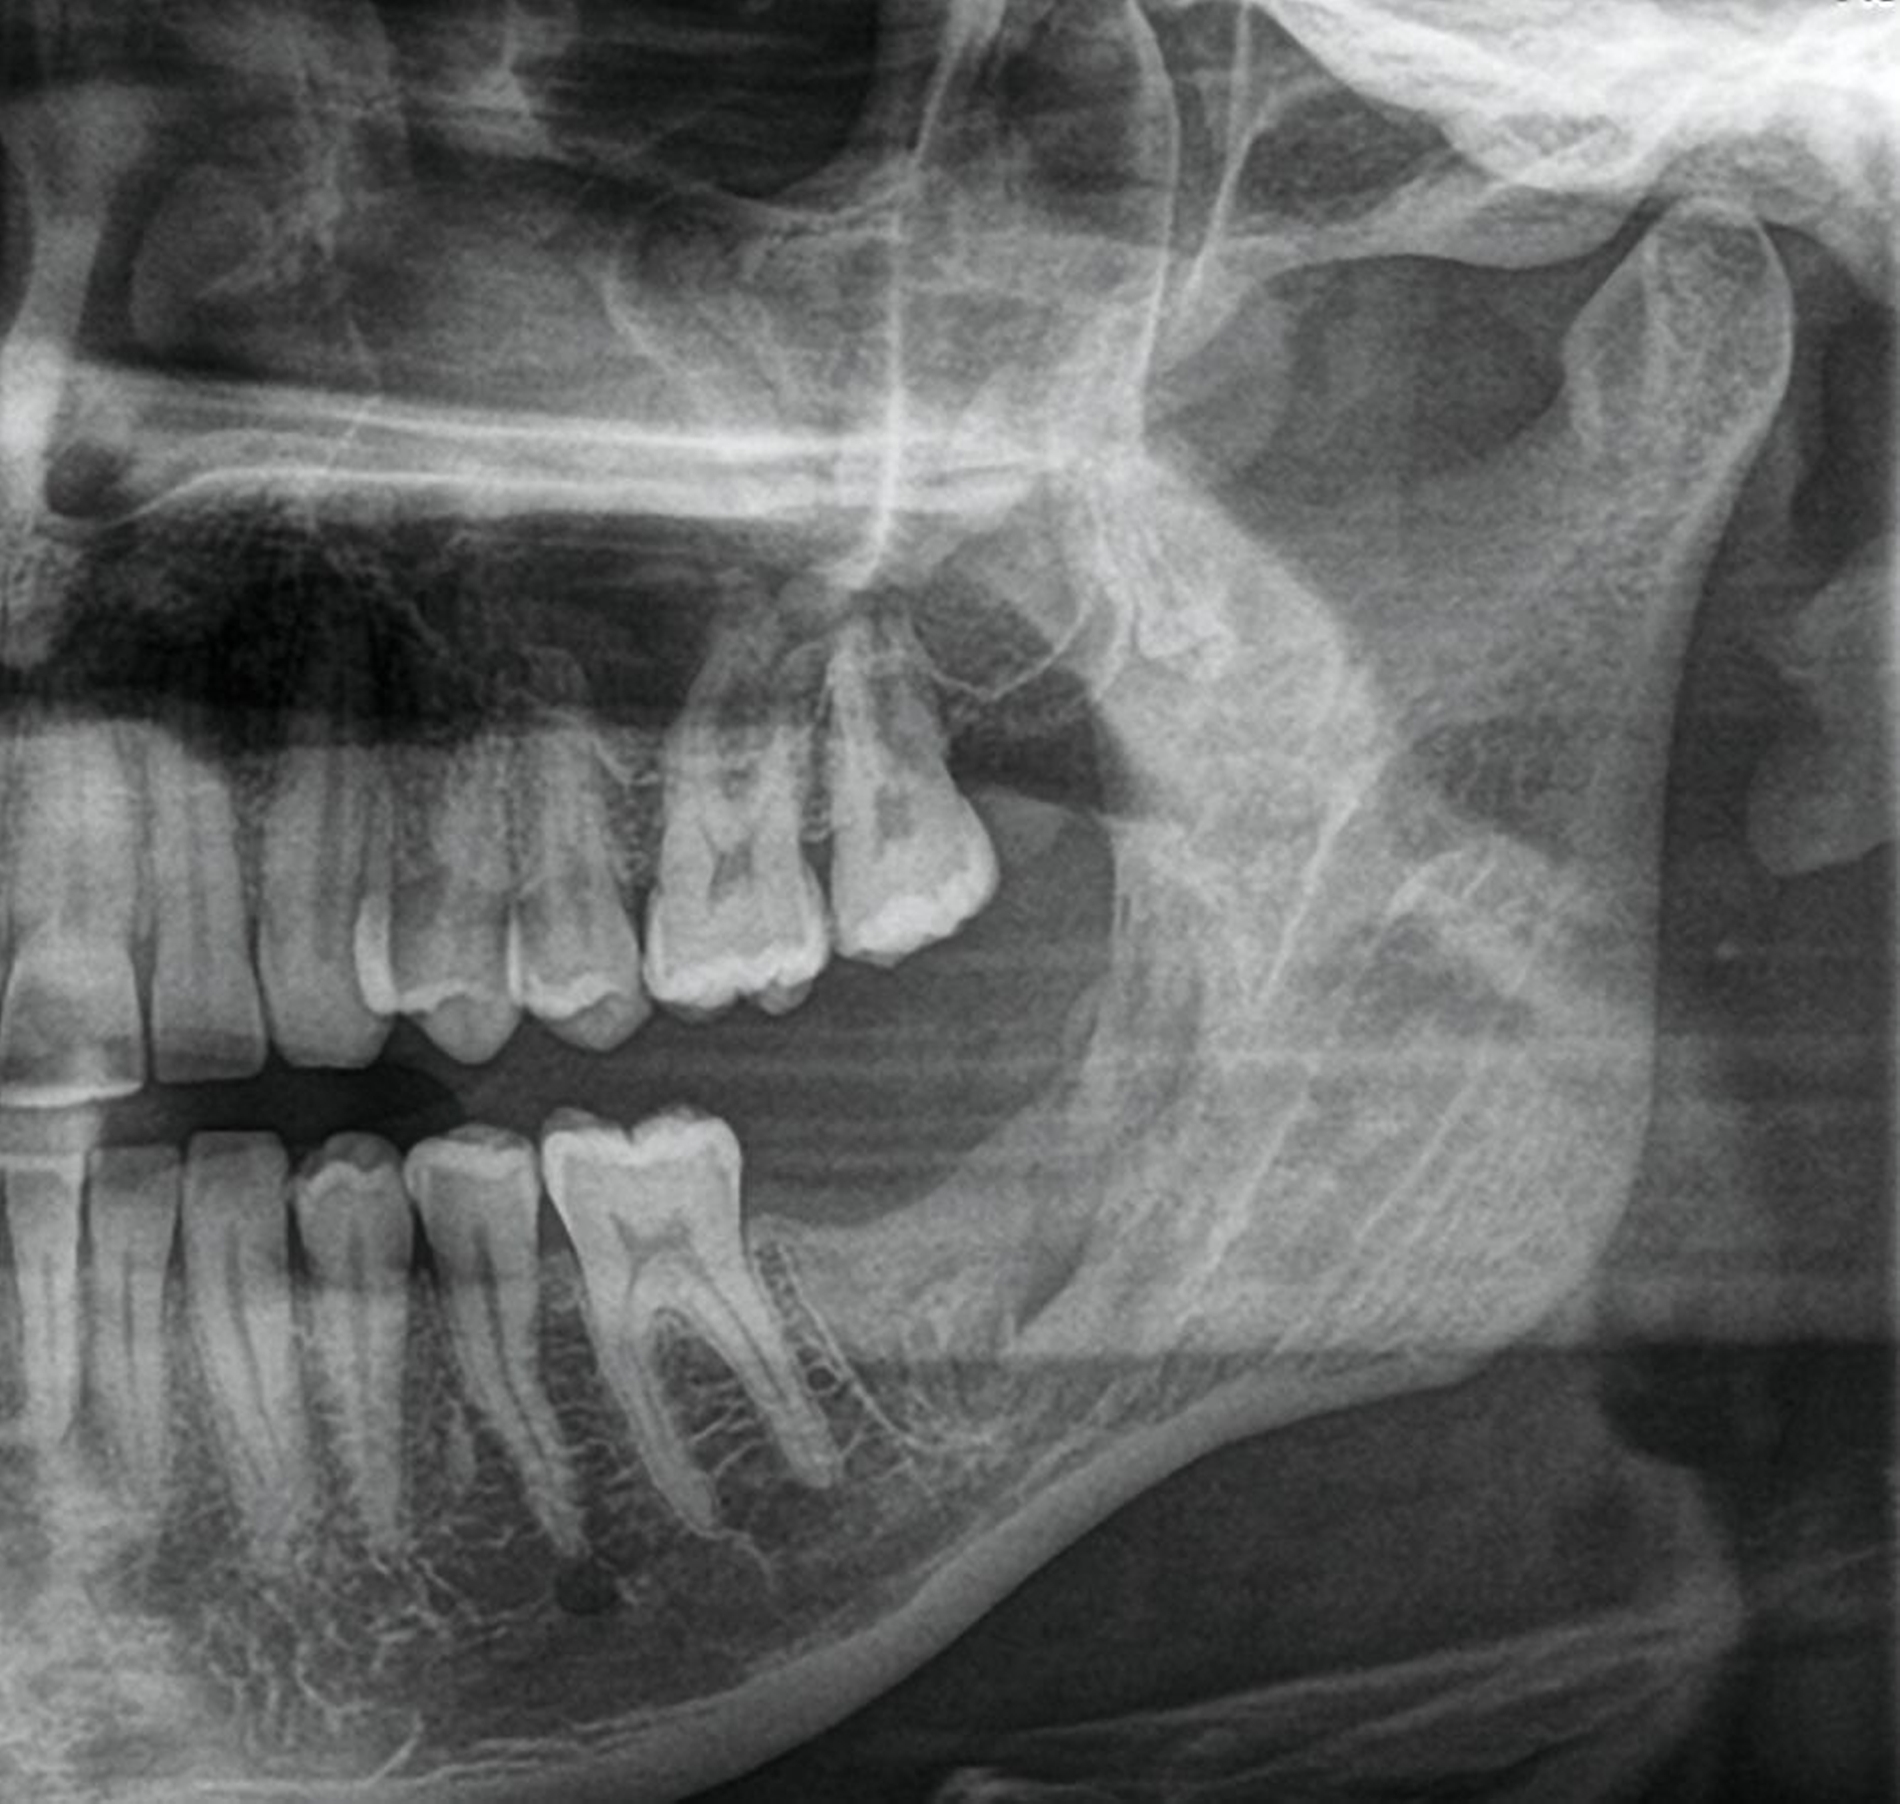

Die digitale Volumentomografie (DVT) ergab eine mehrkammerige, radioluzente Raumforderung, die sich bei erhaltener Kortikalis von der mesialen Wurzel des Zahnes 37 bis in den aufsteigenden Ast des Ramus mandibulae erstreckte (Abbildungen 1 und 2). Aufgrund der Morphologie bestand der Verdacht auf einen keratozystischen odontogenen Tumor, differenzialdiagnostisch auf andere odontogene Tumoren. Nach Aufklärung wurden die Extraktion des nicht erhaltungswürdigen Zahnes 37 sowie die Zystektomie geplant und zwei Wochen später in Intubationsnarkose durchgeführt.

Die seitdem halbjährlich durchgeführten Nachkontrollen zeigen klinisch reizlose Verhältnisse und einen beschwerdefreien Patienten. Radiologisch fand sich eine fortschreitende knöcherne Ausheilung ohne Rezidivhinweise, wie in den Verlaufskontrollen unmittelbar postoperativ, nach einem Jahr und nach zwei Jahren dargestellt (Abbildung 5). Angesichts möglicher Spätrezidive wird die langfristige Nachsorge fortgeführt.